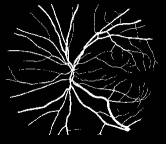

Refer to caption

Figure 1: Vessel segmentation results of side-output(s-out) layers produced by three networks. From top to bottom the network is normal DSN (with no short connections), BS-DSN (DSN with bottom-top short connections) and BTS-DSN (DSN with both bottom-top and top-bottom short connections), respectively.

As pointed out in recent works [15, 17], a good semantic segmentation network should learn multi-level features. Further, it should have multiple stages with different receptive fields to learn more inherent features from different scales. FCN, taken as an example, uses skip connections to fuse multiple stages outputs, as well as the HED network, in which a series of side-output layers are added after each stage in VGGNet. The HED network was first proposed for edge detection, and further used for image-level vessel segmentation in recent studies [6, 16], with significant performance. However, our experimental results show that such network architecture is not appropriate for vessel segmentation directly. Figure 1 provides such an illustration. Reasons for this phenomenon are straightforward. On one hand, the side-output of the first layer often contains too many noises. On the other hand, the features produced by the last side-output layer are too coarse due to information loss of pooling operation. Obviously, the inaccurate vessel map of side-output1 and side-output4 should have negative impacts on the final segmentation result.

In addition, we can observe from Figure 1 that the side-output1 and side-output4 of the BTS-DSN were more accurate compared with those of the DSN.